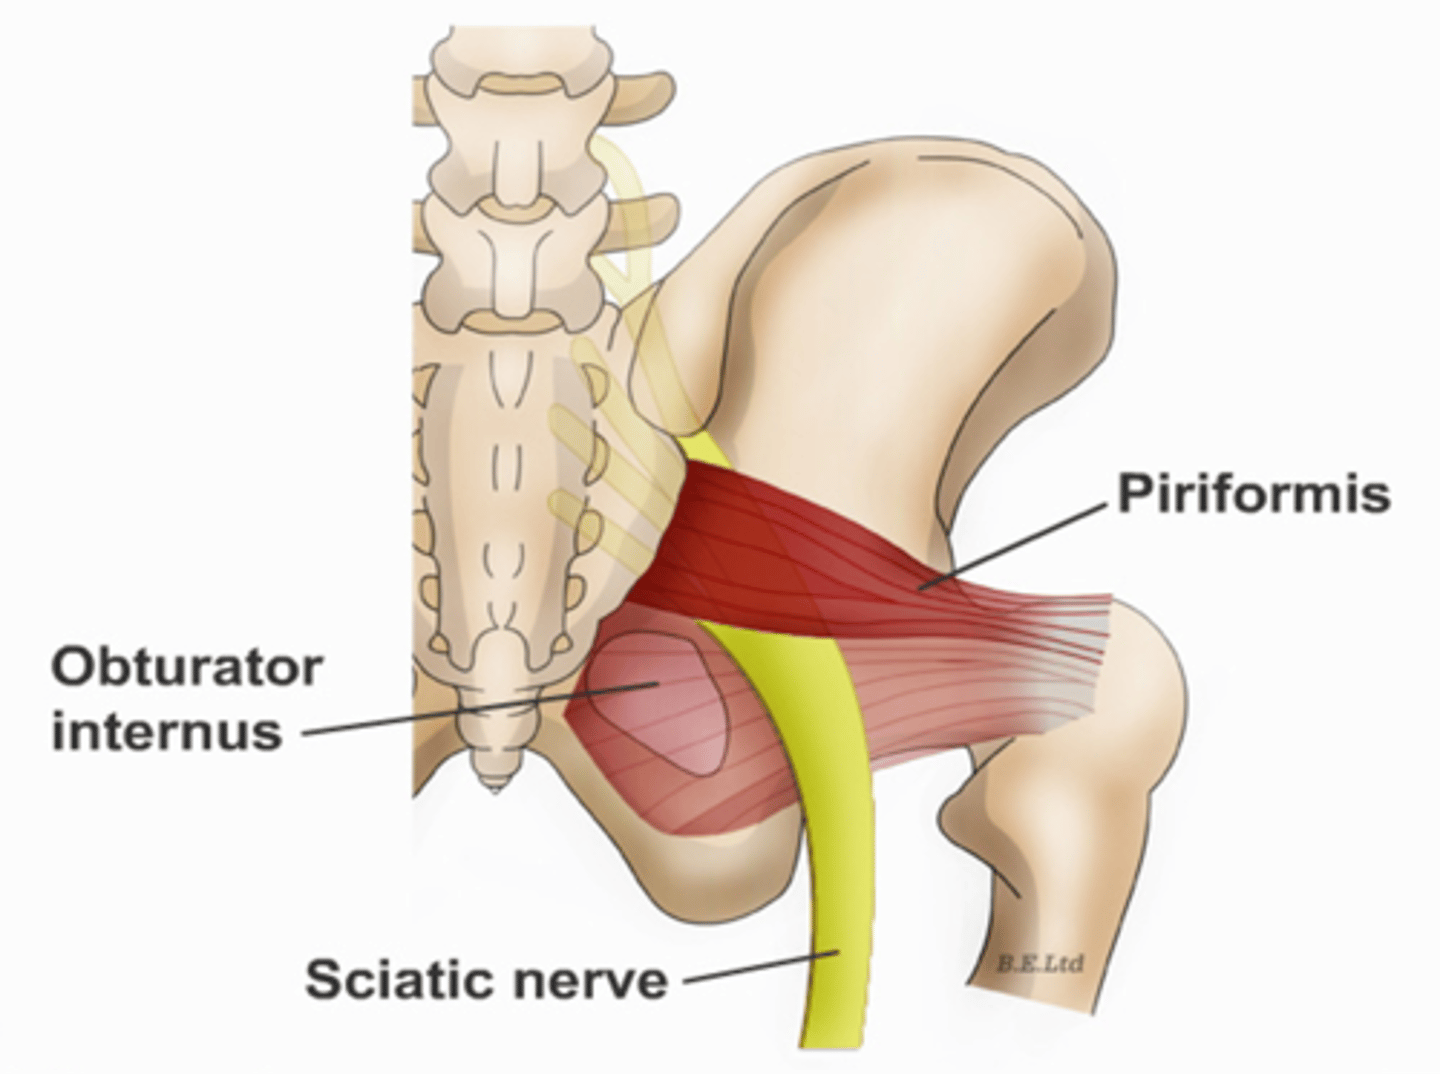

Obturator internus muscles line the ___ walls of the true pelvis

lateral

Piriformis muscles are in the ___ region of the true pelvis behind the ___

posterior; uterus

What muscle is often mistaken for ovaries?

piriformis